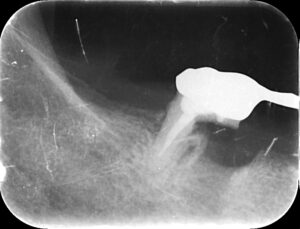

そのため歯茎を開いて根っこだけを削って抜歯する処置を

行いました。

抜歯をし歯が出ています。

抜歯を終え縫合を終えたところです。

レントゲンで根が半分抜けているのが

わかります。

この場合は被せてあるブリッジを外さす抜歯が

行えました。

しかし支える根が減りますので、あまり長くは

持たないかもしれません。

しかしブリッジを外さないで抜歯を行ったため

患者様が噛みにくくなることを極力避けている

ことになります。